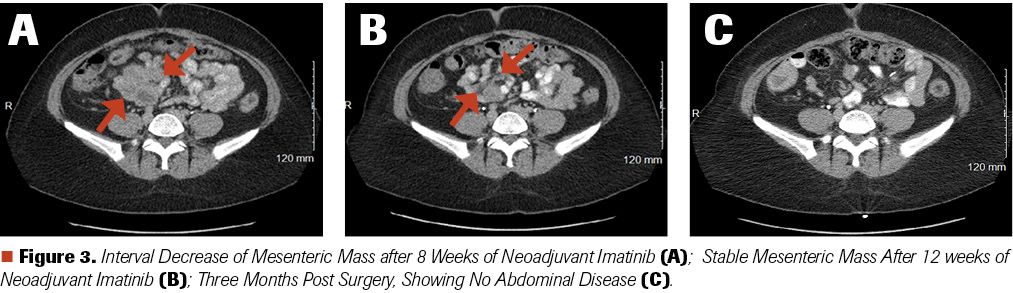

After 8 weeks of neoadjuvant therapy with imatinib 800 mg by mouth (po) daily, CT scans showed interval decrease in the patient’s mesenteric mass, down to 8.3 x 6.2 cm (Figure 3A). After another 4 weeks of neoadjuvant imatinib, CT scans did not show any further significant decrease in the size of the mass (8.1 x 6.2 cm) (Figure 3B).

Figure 3. Interval Decrease of Mesenteric Mass after 8 Weeks of Neoadjuvant Imatinib (A); Stable Mesenteric Mass After 12 weeks of Neoadjuvant Imatinib (B); Three Months Post Surgery, Showing No Abdominal Disease (C).

After surgery, she was placed on adjuvant imatinib 800 mg daily to be given for the next 3 to 5 years. Her most recent CT scan, done 3 months post surgery, showed no evidence of disease (Figure 3C). The patient expresses her strong desire to be able to conceive and have her own biologic children in the near future.